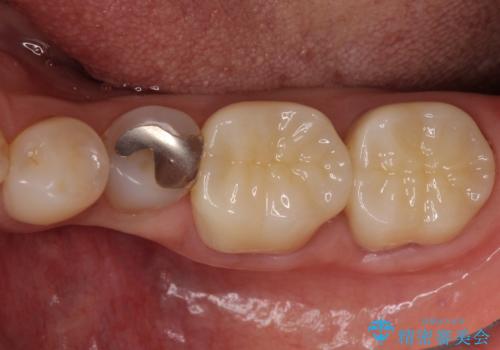

- 上下の奥歯にものが挟まりやすいことを気にして来院された患者様です。

上下ともに、やや大きいむし歯があり、そこにものが挟まりやすくなっていました。

上顎の奥歯は神経にまで虫歯が及んでいる可能性が高かったため、抜髄や断髄の可能性を考慮しながら処置を進め、セラミッククラウンにて補綴することとしました。

上の奥歯は一部神経を取り除くこととなりましたが、残った神経は正常な状態を保つことができました。